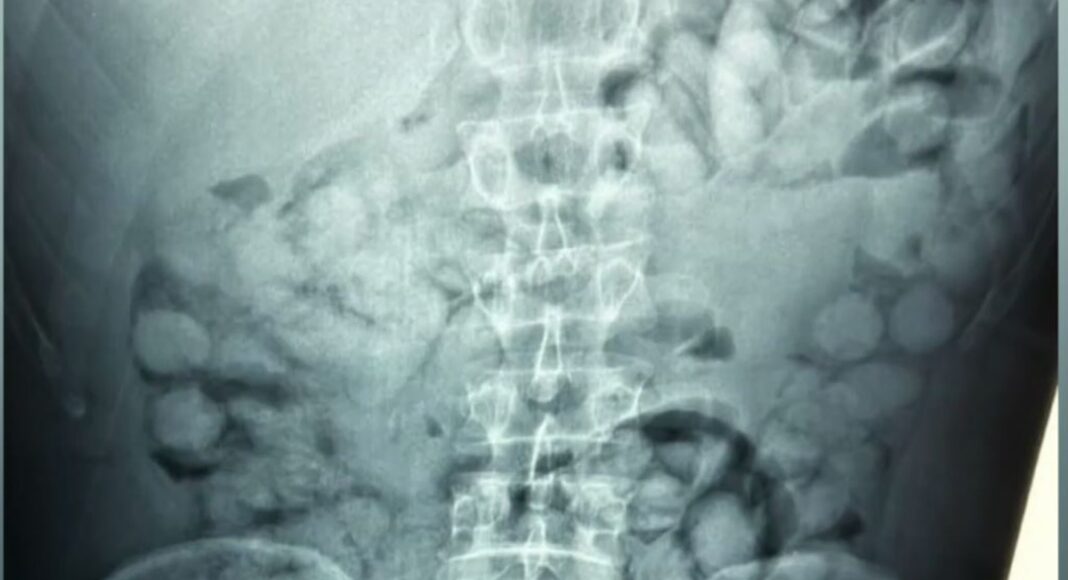

Σύμφωνα με τη δήλωση της ΕΛΑΣ, ο άνδρας έφτασε στην Αθήνα μέσω Παρισιού και, κατά τη διάρκεια του ελέγχου στο αεροδρόμιο, αποκαλύφθηκε ότι είχε μέσα του περίπου 100 συσκευασίες κοκαΐνης. Οι αρχές διαπίστωσαν την ύπαρξη των ναρκωτικών μέσω ειδικών τεχνικών διάγνωσης, που εφαρμόζονται σε ύποπτους επιβάτες διεθνών πτήσεων. Η ΕΛΑΣ υπογράμμισε τη σοβαρότητα της υπόθεσης, σημειώνοντας ότι οι δράσεις αυτής της φύσης αποτελούν άμεση απειλή για τη δημόσια ασφάλεια και υγεία. Οι έρευνες συνεχίζονται για να διαπιστωθούν οι διασυνδέσεις του συλληφθέντα και να εντοπιστούν οι υπεύθυνοι του κυκλώματος διακίνησης.